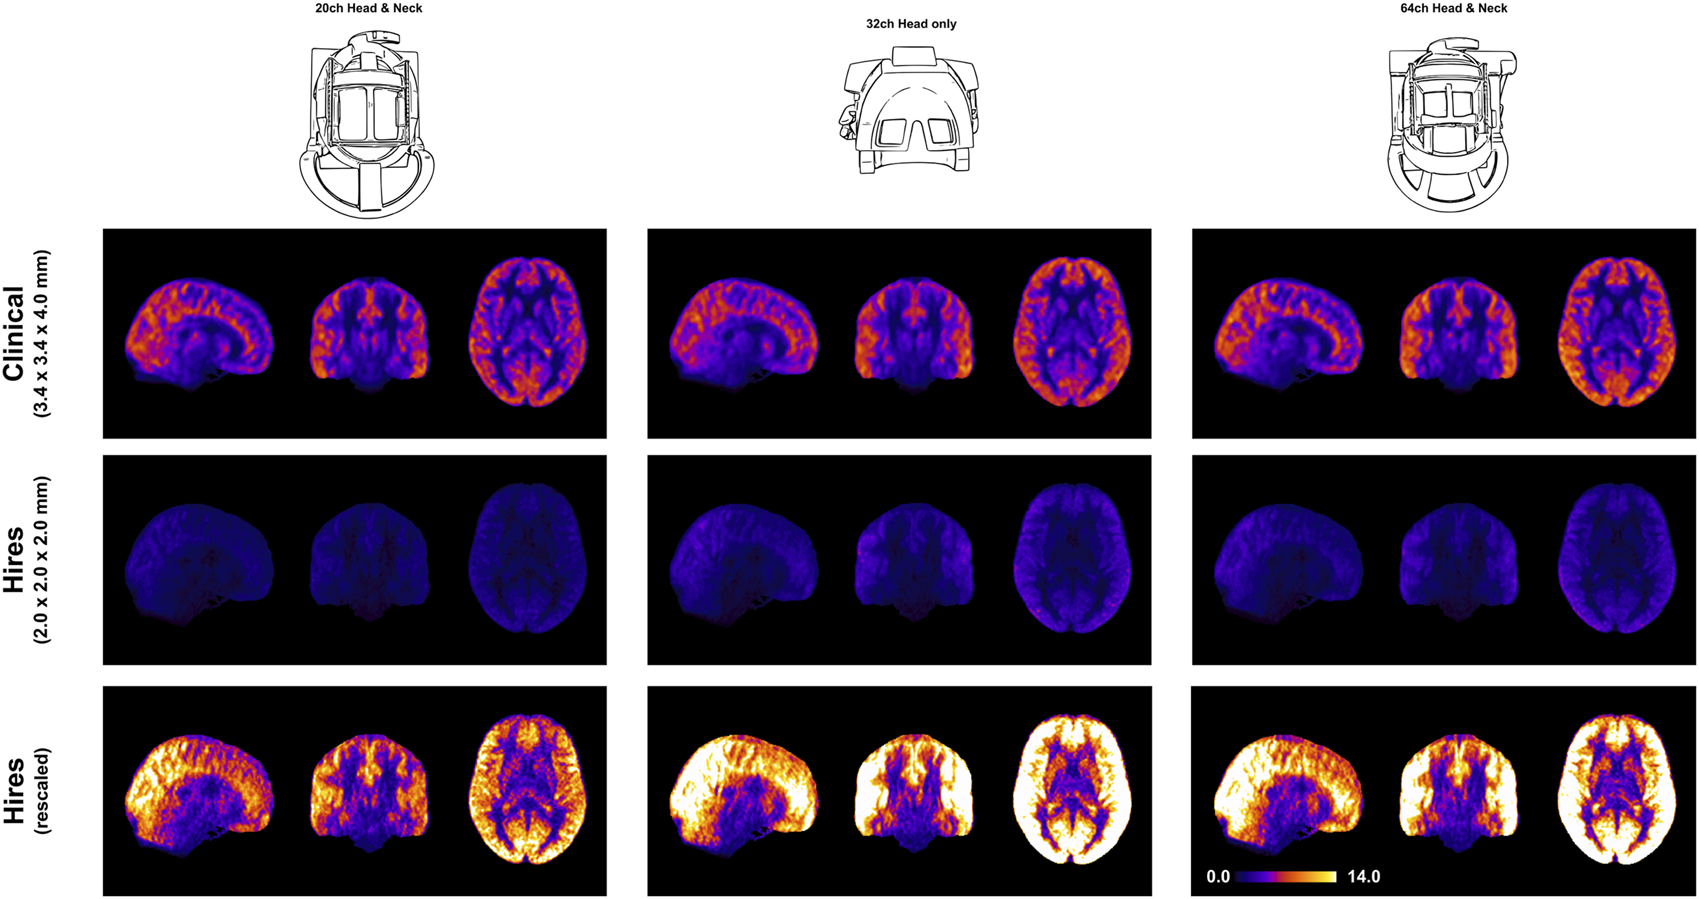

Figure 1 demonstrates that robust CBF maps can be acquired independently of the coil choice. However, the spatial distribution of the CBF maps from the hires protocol shows a preference for 32 and 64ch. Figure 4 (top and middle rows) illustrates the impact of perfusion tSNR across the three coils. In the case of the clinical protocol, the increasing coil count has ≈ 2–2.5% gain in perfusion tSNR, whereas the hires protocol has ≈ 34–42% gain in perfusion tSNR with increasing coil count (Supplementary Table S5). The perfusion tSNR maps of the hires data, rescaled by the ratio of voxel volume (Figure 4, bottom row), illustrate the improvement of tSNR with 32 and 64 coils over 20ch. In addition, Supplementary Table S4 shows that the inter-quartile range (IQR) of the perfusion weighting increases with increasing coil count (20/32/64 ch: for clinical, 312.50/334.30/338.79 a. u., and for hires, 386.34/423.67/440.03 a. u.) for both protocols. The IQR of perfusion weighting between the three coils behaves similarly with the hires PASL protocol (20/32/64 ch: 396.12/447.66/454.97 a. u., Supplementary Table S9). Therefore, it is the SNR benefits afforded by higher coil count rather than the quality or type of labeling used that is responsible of the improvement in the higher IQR of perfusion values.

FIGURE 4

Orthogonal views of the group average perfusion tSNR maps (n = 8) where the pCASL clinical and hires maps are presented in the top and middle rows, respectively. The bottom row shows the hires tSNR data (middle row) but with rescaled values.

We demonstrate that robust rCBF maps can be acquired independently of the coil choice (Figure 1); however, higher coil counts (32 and 64ch) offer substantial gains in perfusion tSNR than the 20ch coil (Figure 4). We find that increasing coil count results in ≈ 2–2.5% gain in perfusion tSNR for the clinical protocol compared to ≈ 34–42% gain for the hires protocol (Supplementary Table S5). One reason for this difference could be that data acquired with clinical protocol in Figure 1 are relatively insensitive to the choice of coil due to its low spatial resolution (i.e., low thermal noise) and acceleration (i.e., no g-factor penalty) requirements. On the other hand, the hires protocols accelerate higher and have increased thermal noise than the clinical protocol, owing to the smaller voxel sizes, and therefore benefit from the increased number of coils (Figure 4).

Interestingly, Figure 4 shows that reducing the voxel size (i.e., higher spatial resolution) actually results in a gain in perfusion SNR (clinical vs. hires (scaled)), which may seem counterintuitive from the standpoint of conventional fMRI where the SNR of the BOLD signal decreases with increasing resolution. However, this is due to the different signal origins of the BOLD and perfusion contrasts. By reducing PV with veins and macro-vasculature, we are reducing the signal contributors of the BOLD signal, whereas these same signal components are sources of noise in perfusion imaging, as they have very low perfusion signals. In addition, reducing WM contribution of voxels dominated by GM improves the fidelity of GM perfusion values and reduced influence of physical noise stemming from WM. Therefore, reducing PV increases our sensitivity to the cortical microvasculature signal and reduces noise and signal contribution from WM and CSF. In other words, higher spatial resolution not only decreases image SNR in both BOLD and perfusion methods due to reduction in the number of protons (i.e., voxel volume) but also reduces noise sources in perfusion imaging stemming from CSF, veins, and WM.